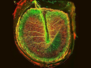

This video shows a mouse lymph node full of stem cell-like memory T cells (TSCM), coloured yellow. These cells are important for long-term immune memory and their generation and maintenance are considered crucial for the lasting protection induced by certain vaccines. It has been reasoned, therefore, that boosting these cells alongside an immunisation could enhance a vaccine’s protective power. And now researchers have figured out how to do just that – by transiently inhibiting interferon-1 signalling upon delivery of a vaccine. Interferons are inflammatory cytokines produced early in infection or immediately following a vaccination and they promote the development of effector T cells [those executing the immune response]. Because these effector cells develop from TSCM cells, it’s thought that transiently blocking their development would enable the precursor TSCM cell numbers to expand. Sure enough, this trick improved vaccine-induced protection against a rodent virus in mice, suggesting it may work in humans too.